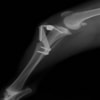

術前左後肢側面像

術後左後肢側面像

術前のTPAは左後肢33.1°右後肢26.8°でしたがTPLO実施により左後肢5.5°右後肢12°に矯正されました。